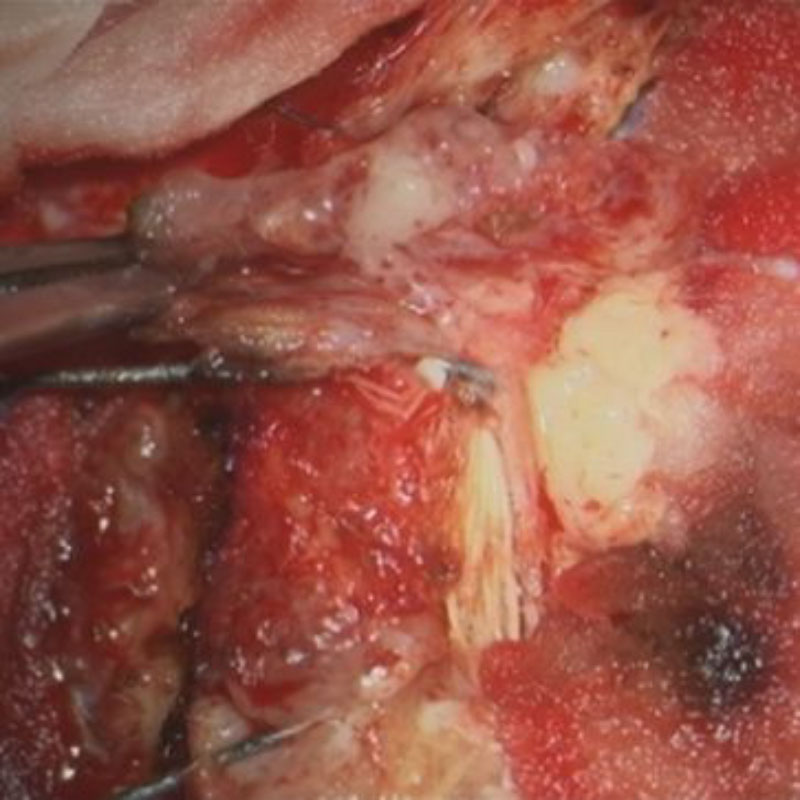

術中写真

No.’24_45 摘出 前

No.’24_45  摘出 中

No.’24_45 摘出 後